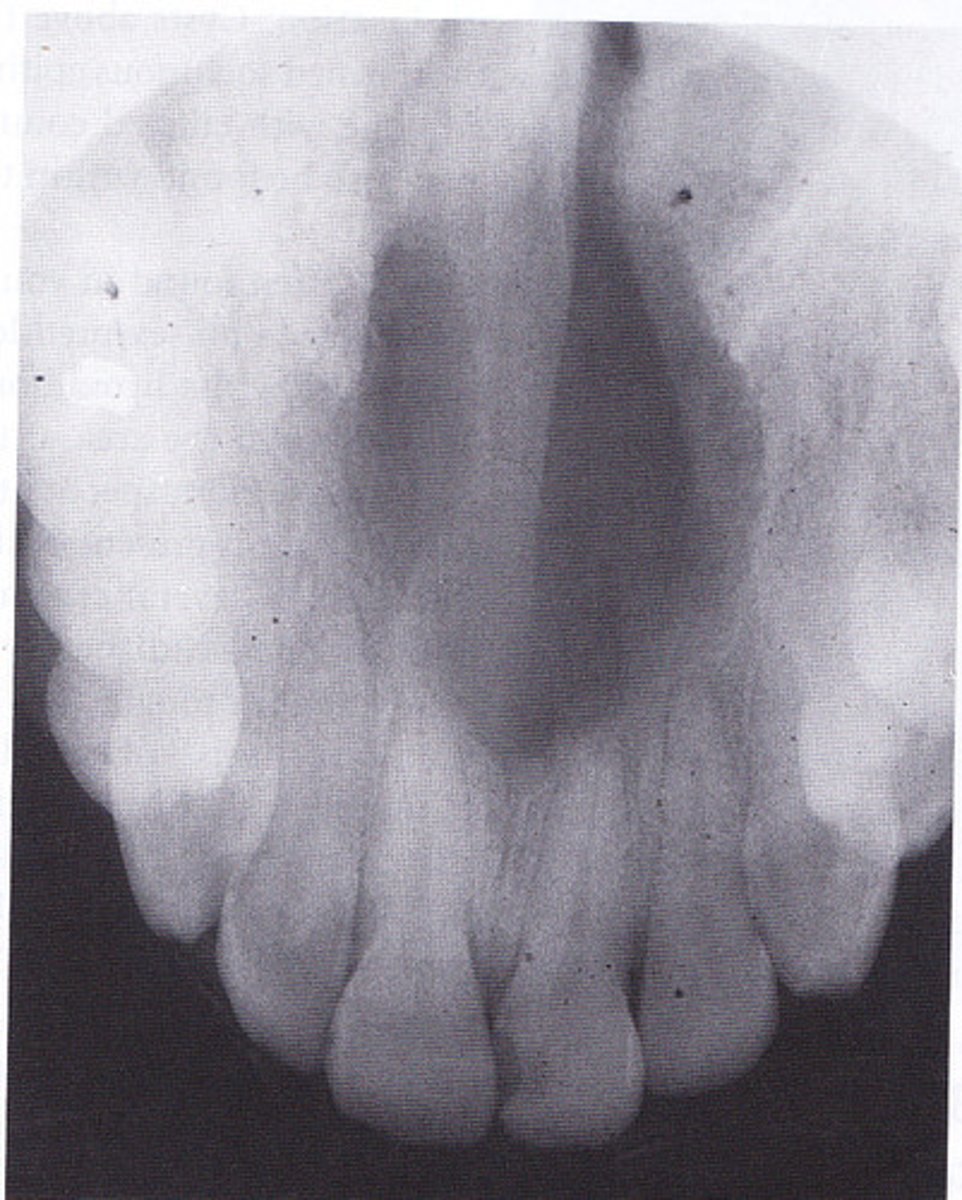

What are radiographic features of nasopalatine duct cysts?

well-defined radiolucency btwn maxillary central incisors

• "heart-shaped" **KNOW FOR EXAM